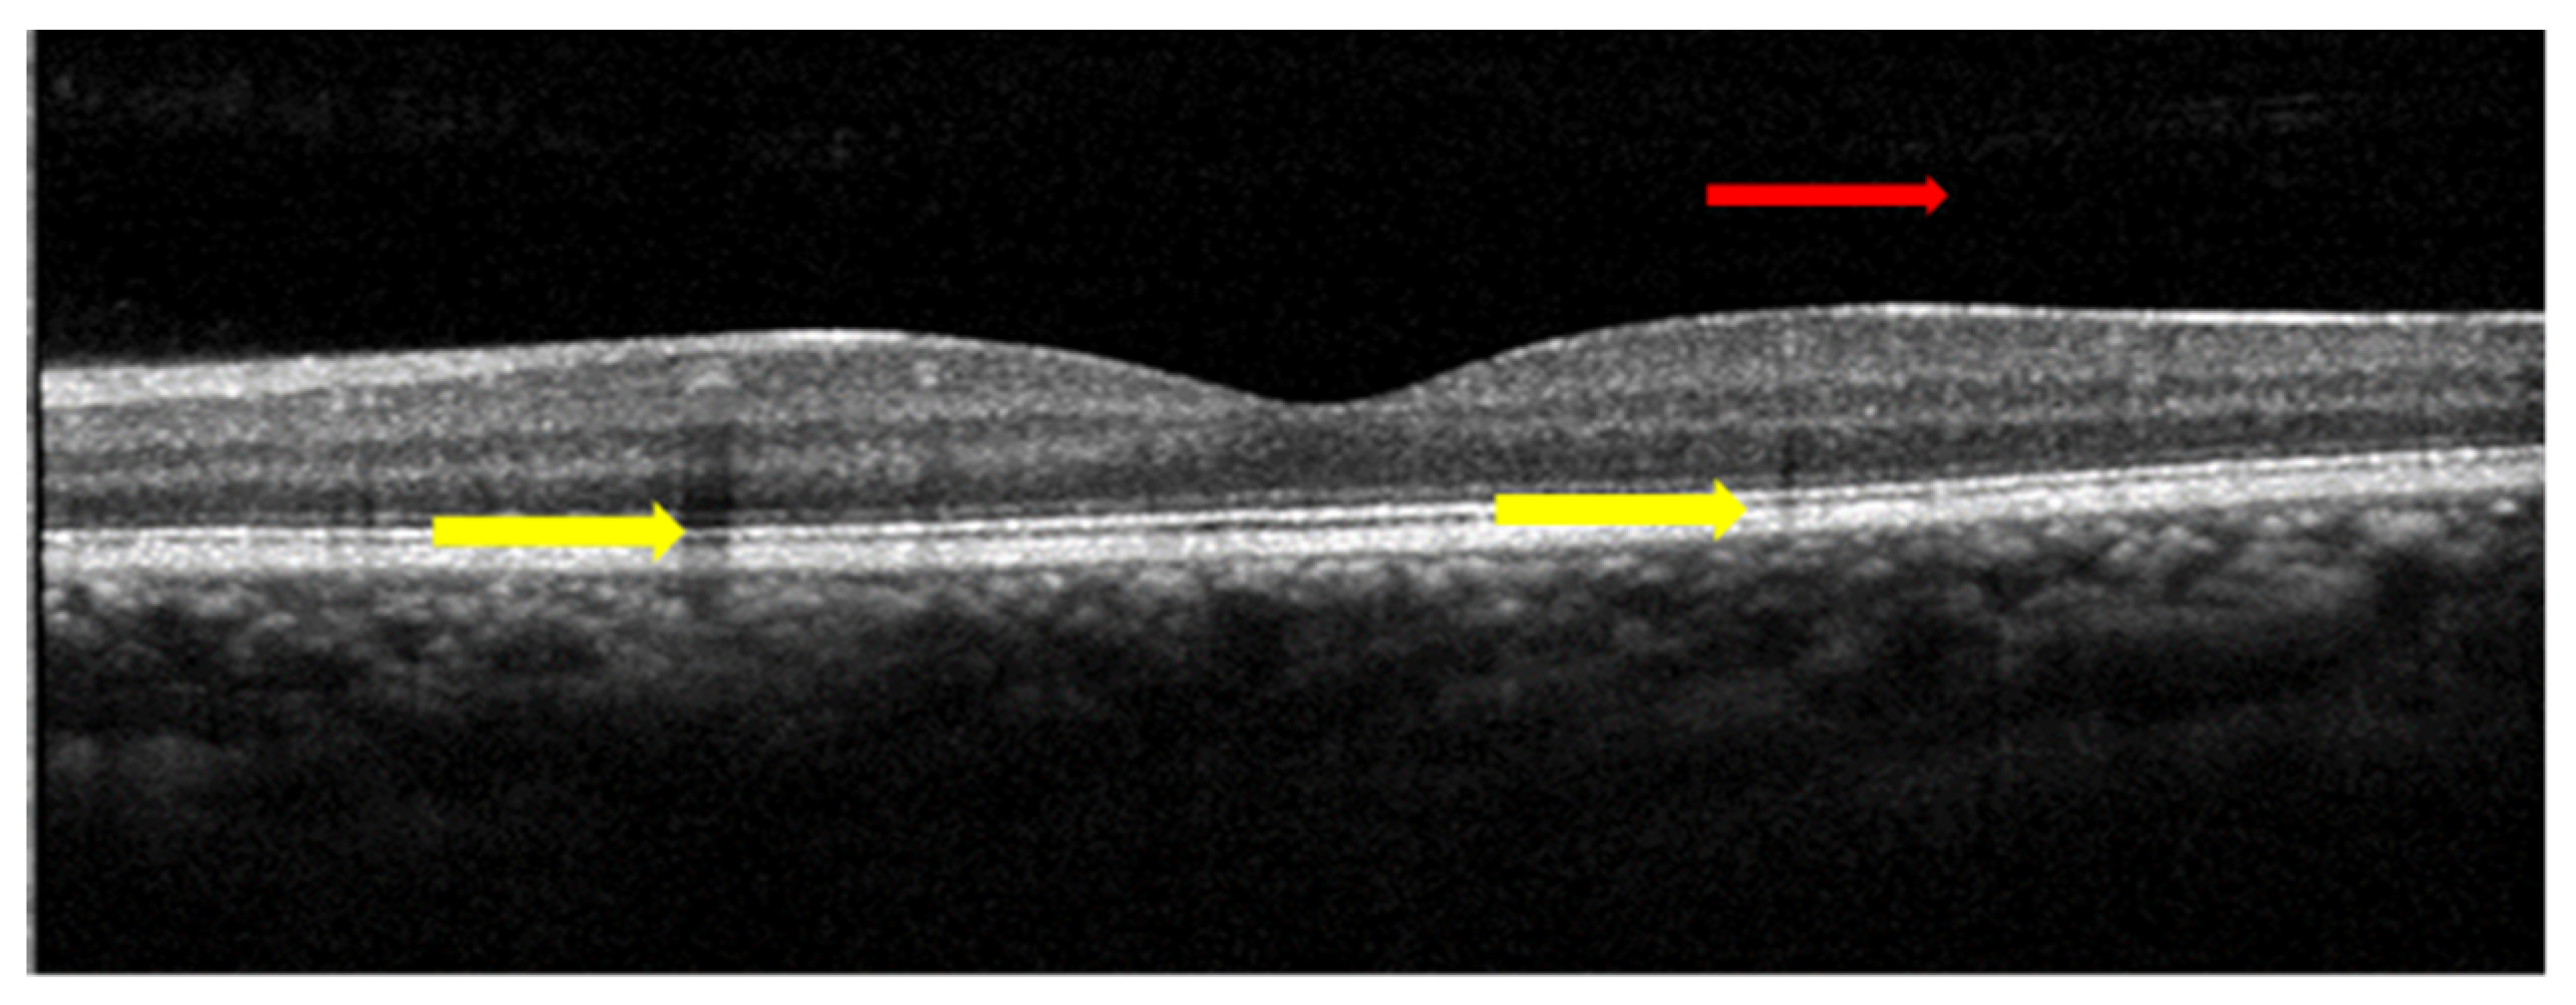

4.2. Segmentation of Subretinal Layers of OCT Images